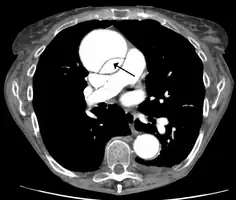

Computed tomography

Computed tomography angiography is a fast, noninvasive test that gives an accurate three-dimensional view of the aorta. These images are produced by taking rapid, thin-cut slices of the chest and abdomen, and combining them in the computer to create cross-sectional slices. To delineate the aorta to the accuracy necessary to make the proper diagnosis, an iodinated contrast material is injected into a peripheral vein. Contrast is injected and the scan performed using a bolus tracking method. This type of scan is timed to an injection to capture the contrast as it enters the aorta. The scan then follows the contrast as it flows through the vessel. It has a sensitivity of 96 to 100% and a specificity of 96 to 100%. Disadvantages include the need for iodinated contrast material and the inability to diagnose the site of the intimal tear.

Aortic dissection

Type A dissection with pericardial effusion as a result.